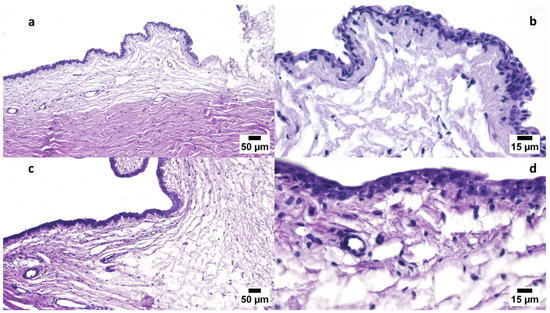

Polymeric Mixed Micelle-Loaded Hydrogel for the Ocular Delivery of Fexofenadine for Treating Allergic Conjunctivitis

This study was designed to formulate a polymeric mixed micelle (PMM) formulation to sustainably release fexofenadine (FEX) to treat allergic conjunctivitis effectively. A 32 factorial design was employed where the studied factors were PL90G amount (X1) and Pluronic (F127 and [...] Read more.

This study was designed to formulate a polymeric mixed micelle (PMM) formulation to sustainably release fexofenadine (FEX) to treat allergic conjunctivitis effectively. A 32 factorial design was employed where the studied factors were PL90G amount (X1) and Pluronic (F127 and P123) mixture ratio (X2), and the dependent variables were entrapment efficacy (EE, Y1, %), particle size (PS, Y2, nm), zeta potential (ZP, Y3, mV), and the percent of drug released after 6 h (Q6h, Y4, %). The optimized formula was blended with a hydrogel base to develop an FEX-PMM hydrogel, where the safety and efficiency of this hydrogel were evaluated using in vivo studies. The EE% of FEX-PMM ranged from 62.15 ± 2.75 to 90.25 ± 1.48%, the PS from 291.35 ± 6.43 to 467.95 ± 3.60 nm, the ZP from −5.41 ± 0.12 to −9.23 ± 0.23 mV, and the Q6h from 50.27 ± 1.11 to 95.38 ± 0.92%. The Draize test results confirmed the safety of the FEX-PMM hydrogel. Furthermore, the FEX-PMM hydrogel showed rapid recovery in animals with induced allergic conjunctivitis compared to the free drug hydrogel. These results assure PMM’s capability to deliver FEX to the conjunctival surface in a sustained pattern, consequently achieving better therapeutic outcomes. Full article